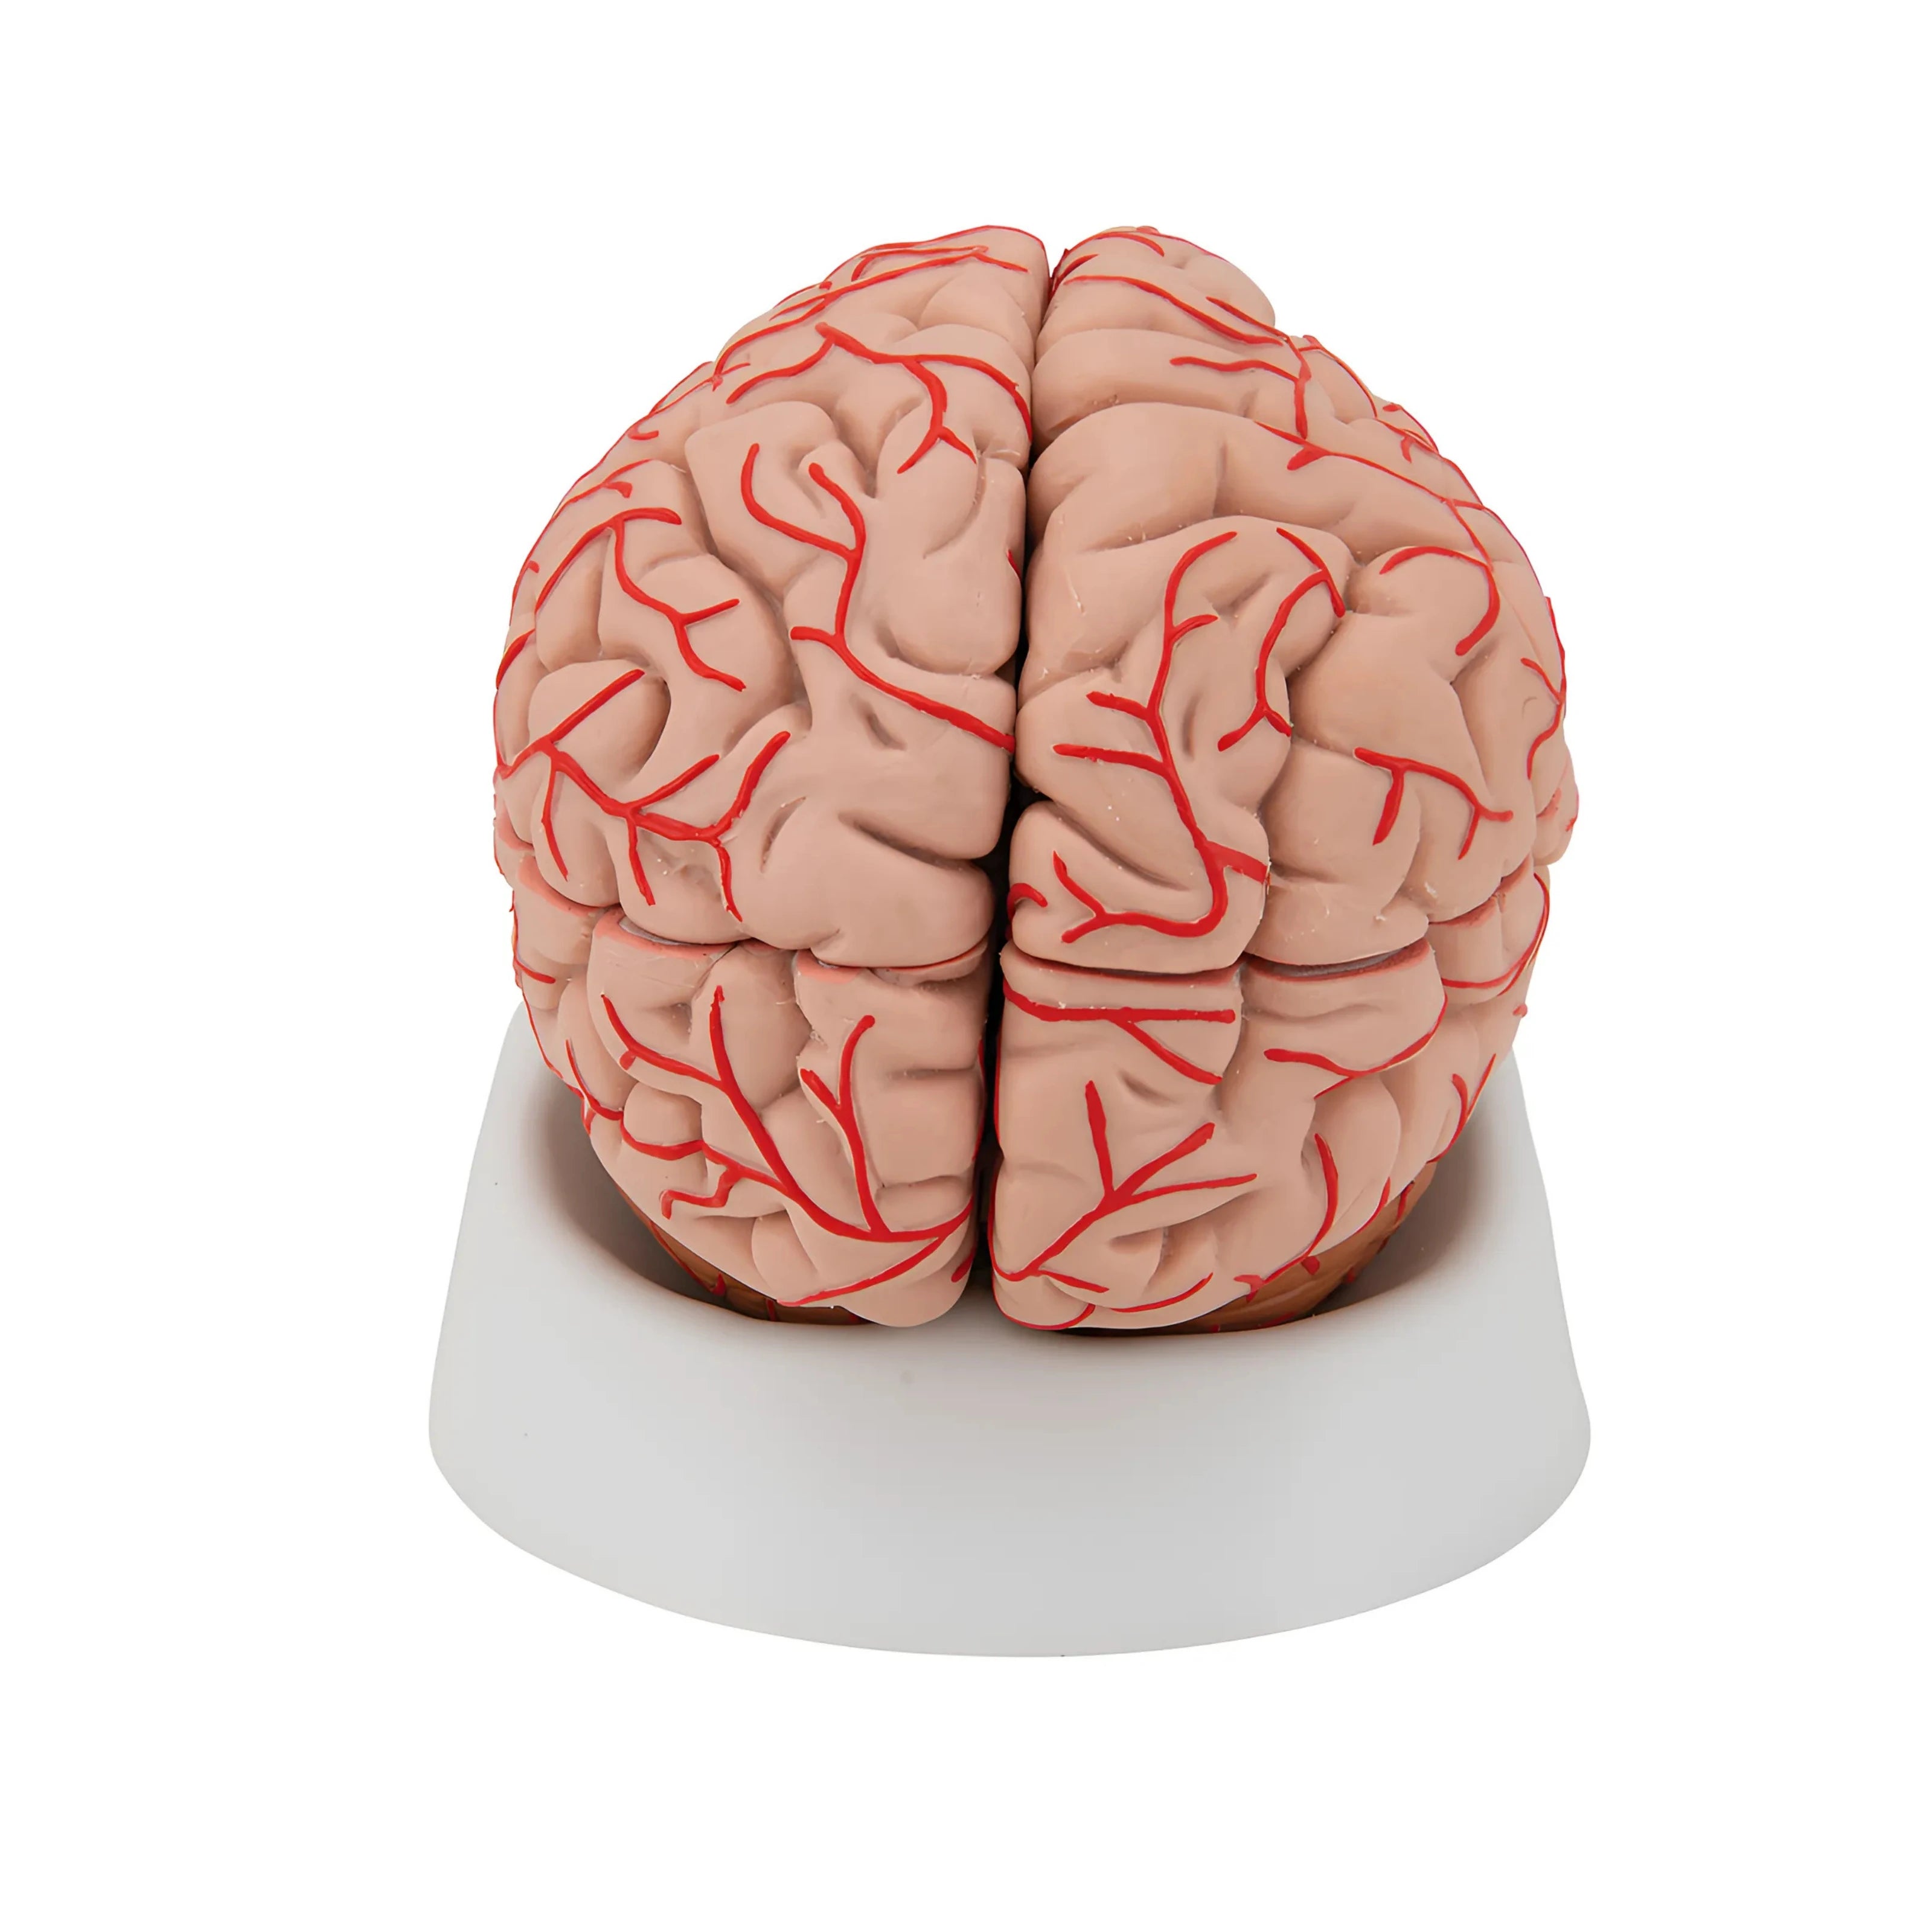

3B Scientific

Cerebro de Lujo con Arterias, desmontable en 9 piezas - 3B Smart Anatomy

Precio de venta$18,177.53